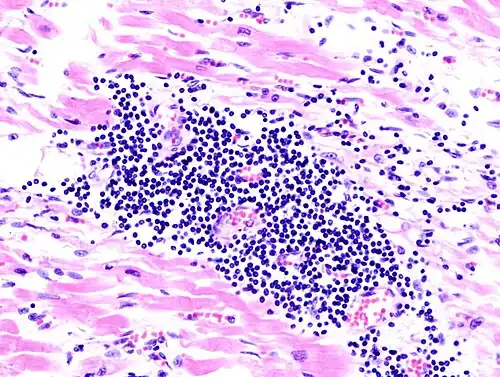

Histologic slide demonstrating viral myocarditis, an infection of the heart muscle